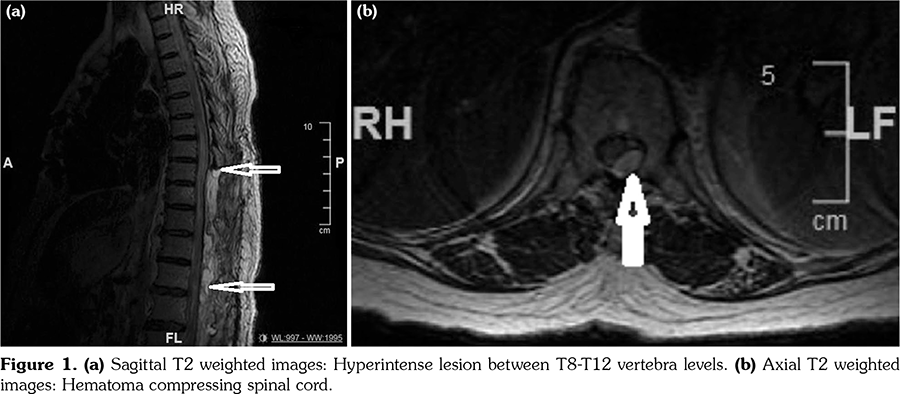

Seven days after the surgery, her symptoms worsened and she also developed arm weakness. Cervical MRI revealed an intramedullary mass between the C5-C7 vertebra levels which was consistent with an abscess (Figure 2) although the CRP levels were within the normal range. She was re-operated and the intradural abscess was drained. The culture of pus from the abscess turned out to be negative. She developed severe pneumonia. The blood culture was negative. One month after the first surgery, Candida albicans was observed in the culture of sputum in the intensive care unit and patient died despite the antifungal treatment.